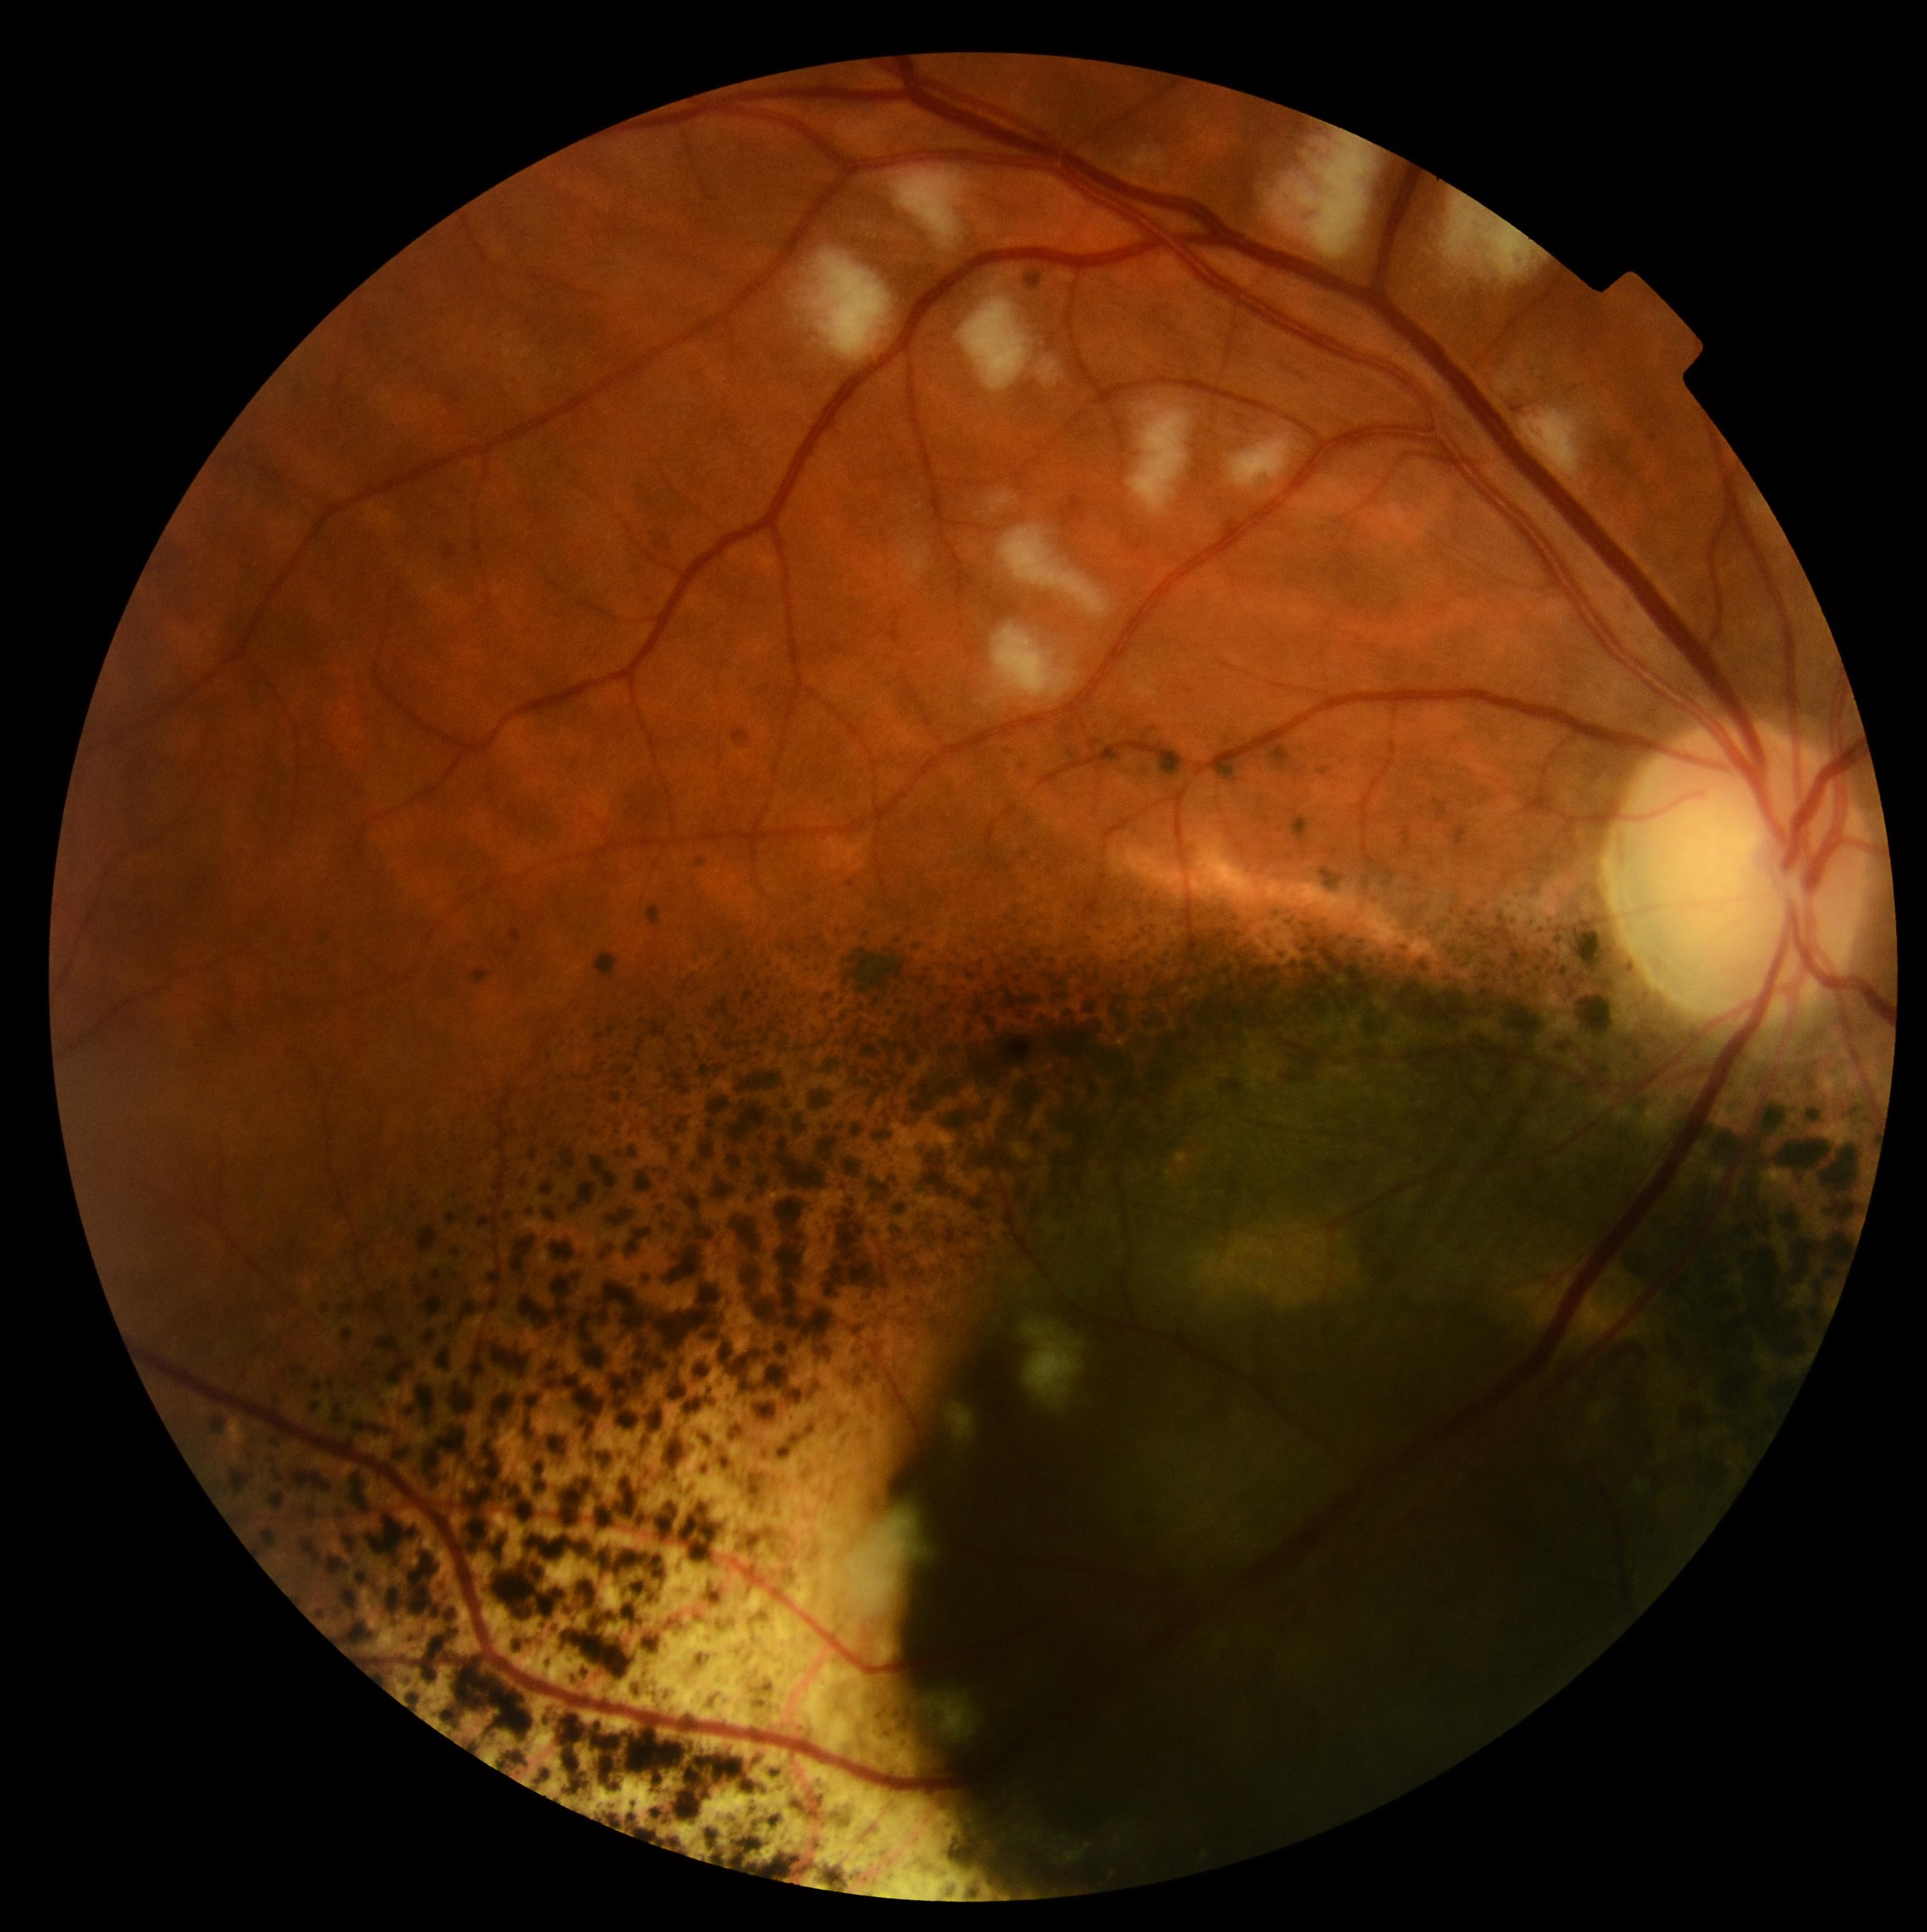

RESULTADOS: Foram submetidos a BTE 22 olhos de 22 doentes, com mediana de idade de 62 anos. O diâmetro e espessura iniciais medianos foram, respectivamente, 11,87 mm (5,92-16,57 mm) e 6,10 mm (2,60-12,67 mm). Nenhum doente apresentava metastização à distância à data do diagnóstico. O tratamento teve uma duração mediana de 118,1 h. Verificou-se diminuição significativa da espessura (1,13 mm, p=0,001) e do diâmetro (2,47 mm, p=0,001). Não ocorreu metastização nem necessidade de enucleação em nenhum dos doentes. A acuidade visual (AV) diminuiu de forma significativa após tratamento (p=0,001). Trinta e seis por cento dos doentes desenvolveram retinopatia da radiação (RR), com um intervalo de tempo mediano de 13 meses desde o tratamento.

CONCLUSÕES: A BTE permite preservação dos olhos e não apresenta complicações agudas significativas. Apesar do curto seguimento, verificamos uma redução significativa das dimensões do tumor. A taxa de complicações tardias, nomeadamente RR é sobreponível à da literatura.